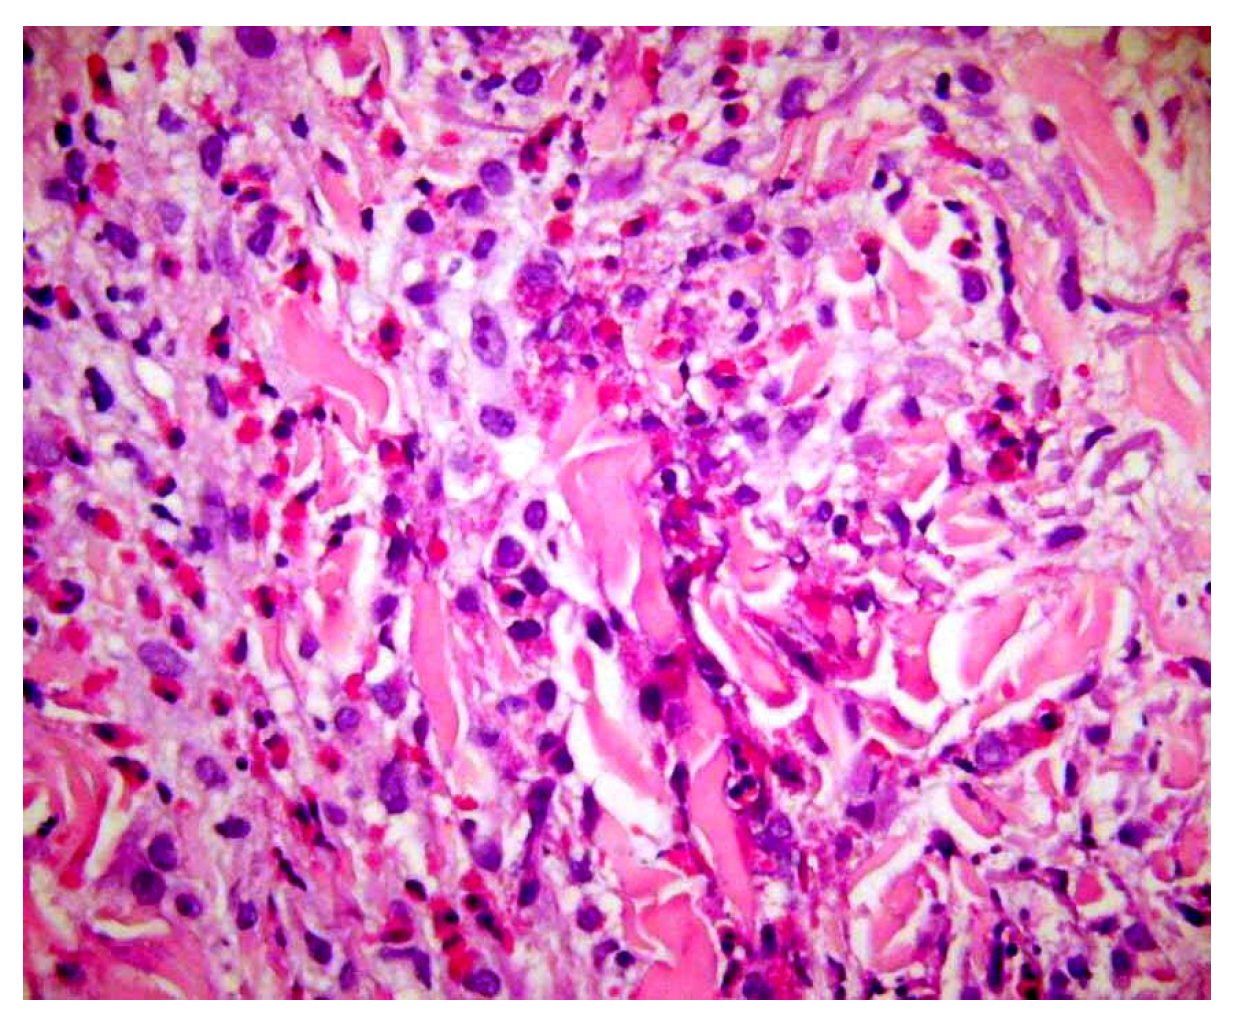

- Presentation: Rapidly enlarging ulcer with undermined violaceous borders and severe pain (Figure 9A).

Figure 9. Ulcerative cutaneous leishmaniasis misinterpreted as pyoderma gangrenosum. (A) A large cutaneous ulcer with a bleeding, fibrinoid bed and an irregular, violaceous, undermined border. (B) High magnification demonstrating Leishmania amastigotes within macrophages. - Abductive step: Pyoderma gangrenosum (PG) is high on the list.

- Deduction: Expect sterile neutrophilic dermal infiltrates; history of IBD or arthritis; paradoxical worsening with surgical debridement; response to steroids.

- Test: Biopsy shows neutrophilic and granulomatous infiltrate (Figure 9B), but treatment fails. Travel history reveals exposure risk. Re-evaluation of sections at high power and Giemsa stain identifies intracellular parasites; PCR confirms Leishmania.

- Update: New abductive hypothesis—cutaneous leishmaniasis—supersedes PG; itraconazole leads to cure.

- Lesson: Nonmonotonicity is not diagnostic failure; it is diagnostic hygiene. Therapy response is itself a test within the ST-Model.